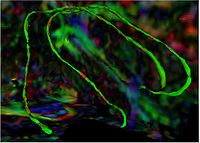

Group Study on DW-MRI using the Tubular Surface ModelWe have proposed a new framework for performing group studies on DW-MRI data sets using the Tubular Surface Model of Mohan et al. We successfully apply this framework to discriminating schizophrenic cases from normal controls, as well as towards visualizing the regions of the Cingulum Bundle that are affected by Schizophrenia. More...

New: V. Mohan, G. Sundaramoorthi, M. Kubicki and A. Tannenbaum. Population Analysis of neural fiber bundles towards schizophrenia detection and characterization, using the Tubular Surface model. Neuroimage (in submission)